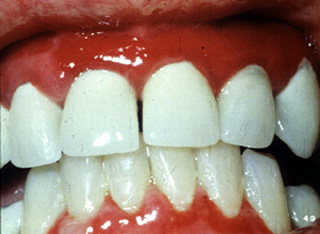

Este paciente también estaba recibiendo un diurético. En este caso la reacción liquenoide  tiene una apariencia muy diferente. Los encía se encuentra muy eritematosa y dolorosa; la ulceración es evidente en la encía marginal. Tras interrumpir el diurético la condición se resolvió.